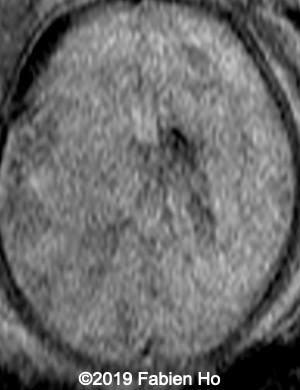

Images 4-11, fetal brain MRI at 28 weeks: the left frontal lesion hence shows DWI hyperintensity, with T2* and T1 peripheral hyperintensity: ischemia with peripheral subacute hemorrhage. Note also that there is an associated blood clot in the left lateral ventricle. There is no obvious mass effect, nor peripheral edema. All these findin>gs are very suggestive of a clastic lesion.

Axial DWI (diffusion weighted imaging): DWI is sensitive to cytotoxic cell edema, found in brain ischemia, among other things.

10

11

Our diagnosis was hence fetal stroke: probably ischemic stroke with secondary hemorrhagic transformation (hemorrhagic stroke could also be a possibility although the absence of mass effect and central lucency without hemorrhagic signal make this hypothesis less likely). Besides, in most pediatric and fetal clastic lesions, hemorrhage and ischemia are associated.